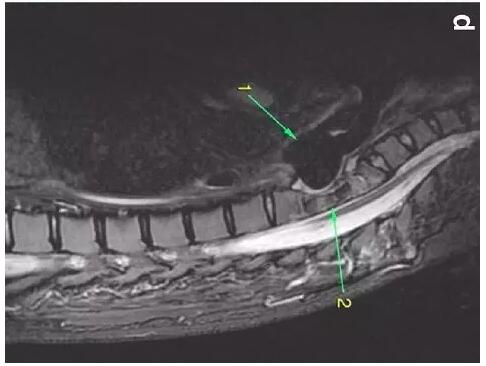

患者入住我院前行胸MRI已經(jīng)發(fā)現(xiàn)類(lèi)似表現(xiàn)(圖d),當(dāng)時(shí)診斷為骨髓炎。

下圖箭頭1為氣切套管氣囊緊貼T1-4椎體水平,造成椎體前部受到侵蝕(箭頭2):